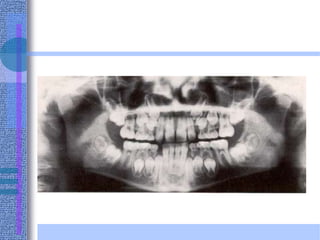

• It is a radiographic procedure that produces a

single image of the facial structures, including

both maxillary and mandibular arches and their

supporting structures.

Indications:

1. Overall view of the teeth and facial bones.

2. Assessment of the presence and the position of multiple unerupted

or impacted teeth.

3. Assessment of gross pathological lesions as cysts or tumours.

4. Radiography of both rami, condyles and coronoid processes and

assessment of any TMJ abnormalities.

5. It reveals fractures of the mandible from the midline to the neck of

the condyle.

6. It reveals the maxillary sinuses, floor of orbits and nasal bone.

7. It demonstrates the presence and progress of any periodontal

disease in an overall way.

8. It is valuable in orthodontics as it reveals the unerupted or absent

teeth and relation of mandible to maxilla.

9. Assessment of degree of alveolar bone and relationship of the

teeth to mental foramen, inferior dental canal and alveolar margin

before implantology.